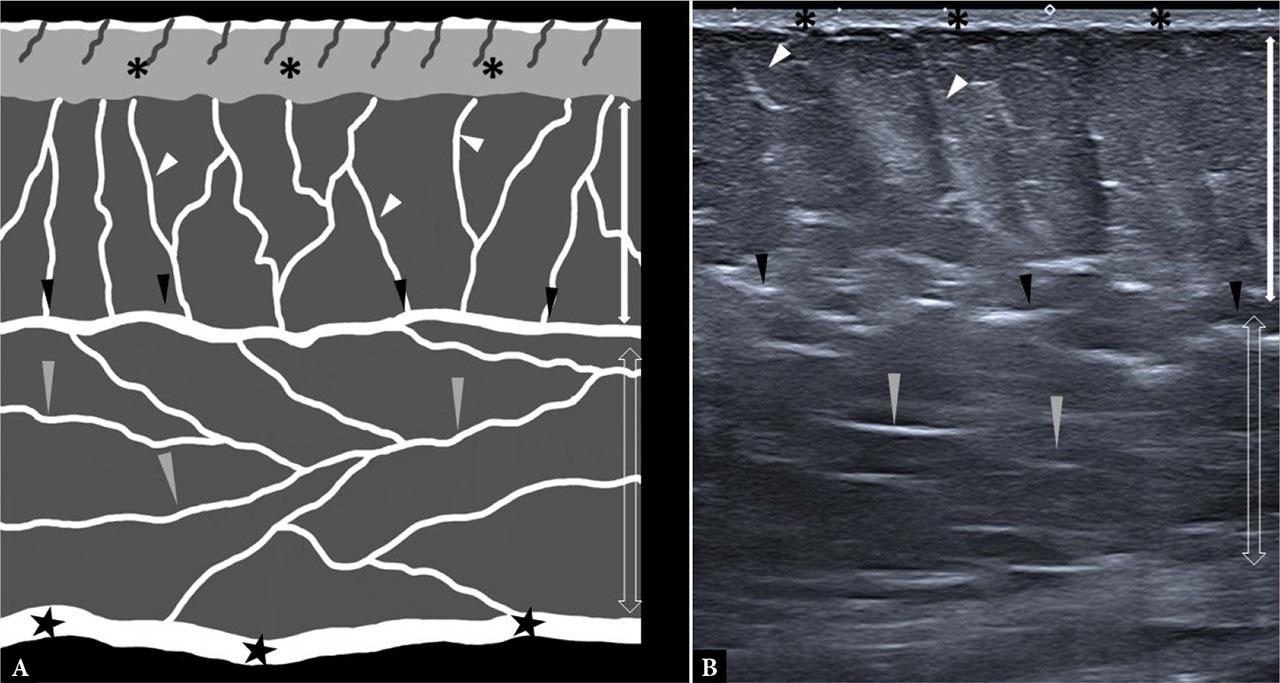

Two adipose layers can be distinguished within the hypodermis, separated by the membranous (superficial) fascia. The superficial layer is composed of large fat lobules divided by thin, predominantly oblique–vertical septa, producing a characteristic honeycomb appearance. It is covered by the membranous fascia, a fibrous sheet rich in elastic fibers and variable in thickness, approximately 0.5 mm at the posterior aspect of the arm. Because this fascia is firmly anchored to both the dermis and the septa, the superficial layer is relatively immobile and provides resistance to external forces(5). Beneath it lies the deep adipose layer, where lobules are smaller, flatter, and less well defined. The septa are thinner and more oblique–horizontal in orientation. Unlike the superficial layer, this deeper tissue is highly mobile, allowing the skin to glide freely over the underlying musculoskeletal structures(6) (Fig. 1).

A. Schematic drawing of subcutaneous adipose tissue and its two layers: SSAT (white double arrow) and DSAT (hollow double arrow); perpendicular interlobular septa in the SSAT (white arrowheads) and oblique interlobular septa in the DSAT (grey arrowheads); superficial fascia (black arrowheads) and deep fascia (black stars); B. Corresponding ultrasound image at the upper aspect of the thigh

On ultrasound, the subcutis appears as hypoechoic lobules separated by hyperechoic fibrovascular septa, producing a honeycomb pattern in the superficial layer. In the deep layer, interlobular septa are more oblique and less distinct. Both layers are separated by the superficial fascia, which appears as a wavy hyperechogenic layer. It is thinner on the dorsal fingers and more abundant in the trunk. Lobule size, shape, and arrangement vary with sex, anatomical site, and depth. Septa serve to anchor the dermis to deeper structures.

Color Doppler often shows hypodermal vessels – thin arteries and larger veins, particularly in the superficial portion – with branches that usually end at the dermal edge. Septal vessels are generally oriented obliquely relative to the aponeurotic surface.